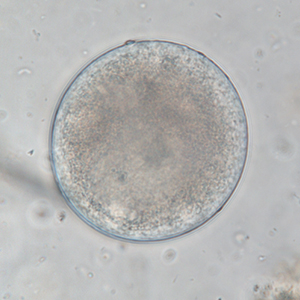

Le kyste est sphérique à ovoïde, à paroi épaisse, mesurant 50 à 100 μm de diamètre. Il présente un contenu granuleux, un macronucléus et micronucléus difficilement visibles (Strait et al., 2012). La coloration au Lugol permet de mettre en évidence certains organites qui apparaissent en brun sombre, de colorer la paroi en brun et l’intérieur du kyste en jaune.